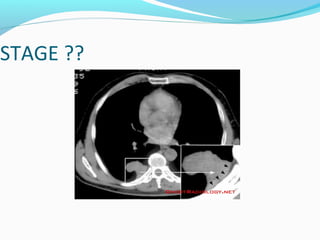

STAGE ??